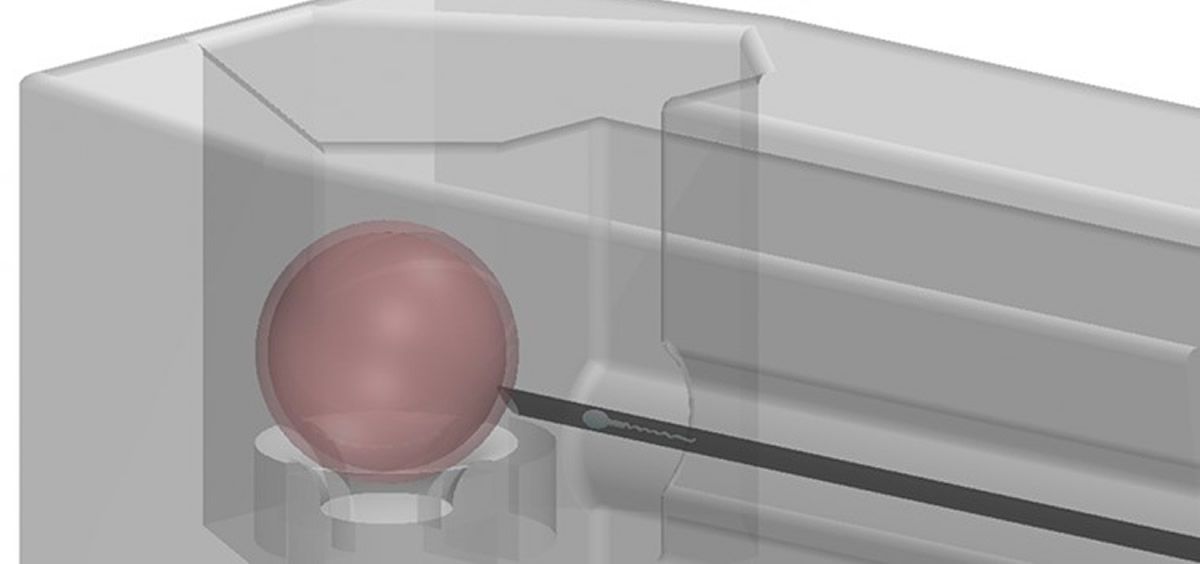

Esta nueva tecnología, más pequeña que la cabeza de un alfiler, mantiene hasta 10 óvulos en posiciones separadas para una inyección más rápida, lo que facilita y permite resultados más reproducibles, lo que puede ahorrar tiempo y recursos dentro de las clínicas de fertilidad. Al eliminar la necesidad de la pipeta que normalmente sostiene el óvulo no fertilizado, este dispositivo simplifica el proceso de inyección, reduce la dependencia de un alto nivel de experiencia técnica y mejorará drásticamente la producción de embriones.

Este nuevo inyector consta de dos componen: “vainas” y un “garaje”. Las cápsulas se pueden usar para cultivar un embrión y se pueden acoplar varias cápsulas dentro del garaje. Los componentes son pequeños ya que cada uno mide menos de un milímetro cúbico, y se fabricaron mediante polimerización de 2 fotones. La tecnología facilita a los embriólogos rastrear lo que están haciendo, evitar errores y hacer que el proceso sea más confiable y repoducible.

Esta nueva tecnología, más pequeña que la cabeza de un alfiler, mantiene hasta 10 óvulos en posiciones separadas para una inyección más rápida